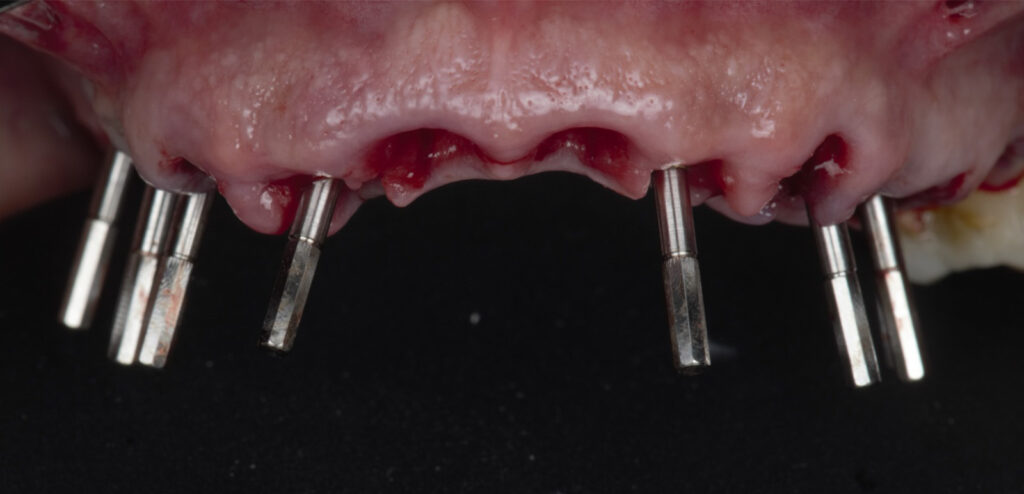

Caso clínico, Dr. José Amador Cabezas

Carga inmediata maxilar con cirugía guiada, registro fotogramétrico y provisionalización inmediata.

En este caso, el Dr. José Amador Cabezas aborda la rehabilitación completa de un maxilar superior comprometido por enfermedad periodontal avanzada, lesiones periapicales y múltiples restauraciones fallidas.

Tras la planificación protésicamente guiada y la colocación de implantes mediante cirugía guiada, se realizó el registro fotogramétrico con T-Marker sobre los Multi-Unit para capturar con precisión la posición real de los implantes y asegurar la pasividad de la estructura provisional.

Gracias a este flujo, el paciente pudo salir de la consulta con una prótesis fija inmediata el mismo día de la cirugía, iniciando así un proceso restaurador más preciso, más predecible y completamente integrado en el entorno digital.

La combinación de cirugía guiada, fotogrametría y carga inmediata permite un control preciso de la posición implantaria y una correcta pasividad protésica desde el primer día.